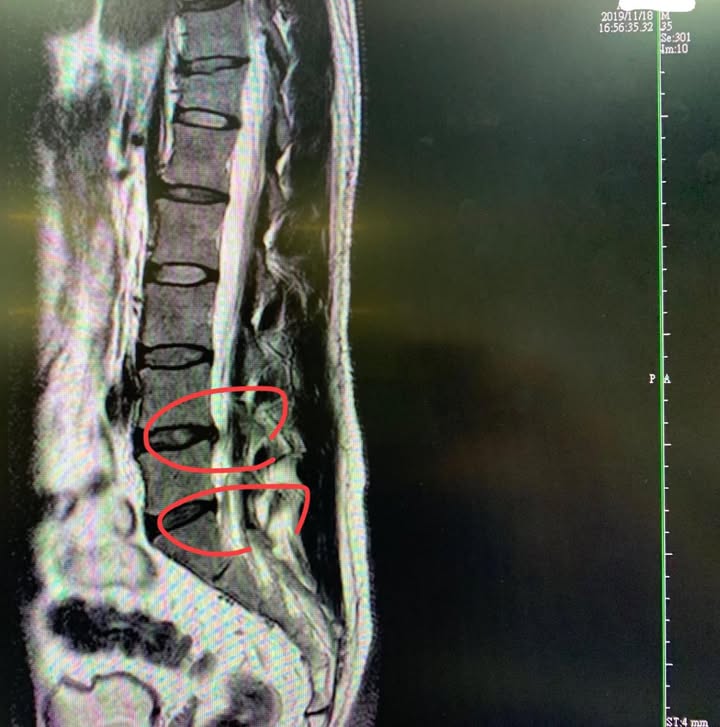

林先生抱怨腰椎疼痛一年多了!之前舊傷從大車滑倒跌落下來撞到導致受傷 ,屁股跟小腿腿肚非常刺痛跟麻痛,以下是做過的治療:傳統針灸..電療...熱療......,以上都是健保治療,所以去好幾個療程,進步很少,想說自費去打PRP(自體血小板生長因子),RRP在台北市診所行情一劑15000,在醫院比較貴會到20000~25000,還打了三次阿,花費不少,根據林先生說法這幾年在治療腰椎花超過快二十萬,後來又在瑞芳小診所打了超過10次消炎止痛針,問題是每次都好一天,隔天開車送貨清運搬東西就開始痛, 整天不定時抽痛,來診前的症狀如下:久站跟走路超過5分鐘開始痛,往後仰跟打噴嚏與咳嗽痛到哀號連連,人生好苦,莫過於開車開不下去~~重點是林先生的職業就是專業開車,每天要開十幾個小時,開車很痛代表他可能無法工作,這對全家經濟命脈都維繫在他身上的林先生很是沉重,這次拿著2019年11月底的核磁共振來接受門診諮詢

診斷:腰椎L4L5 椎間盤突出 (主因)

腰椎L5S1椎間盤膨出 (次因)